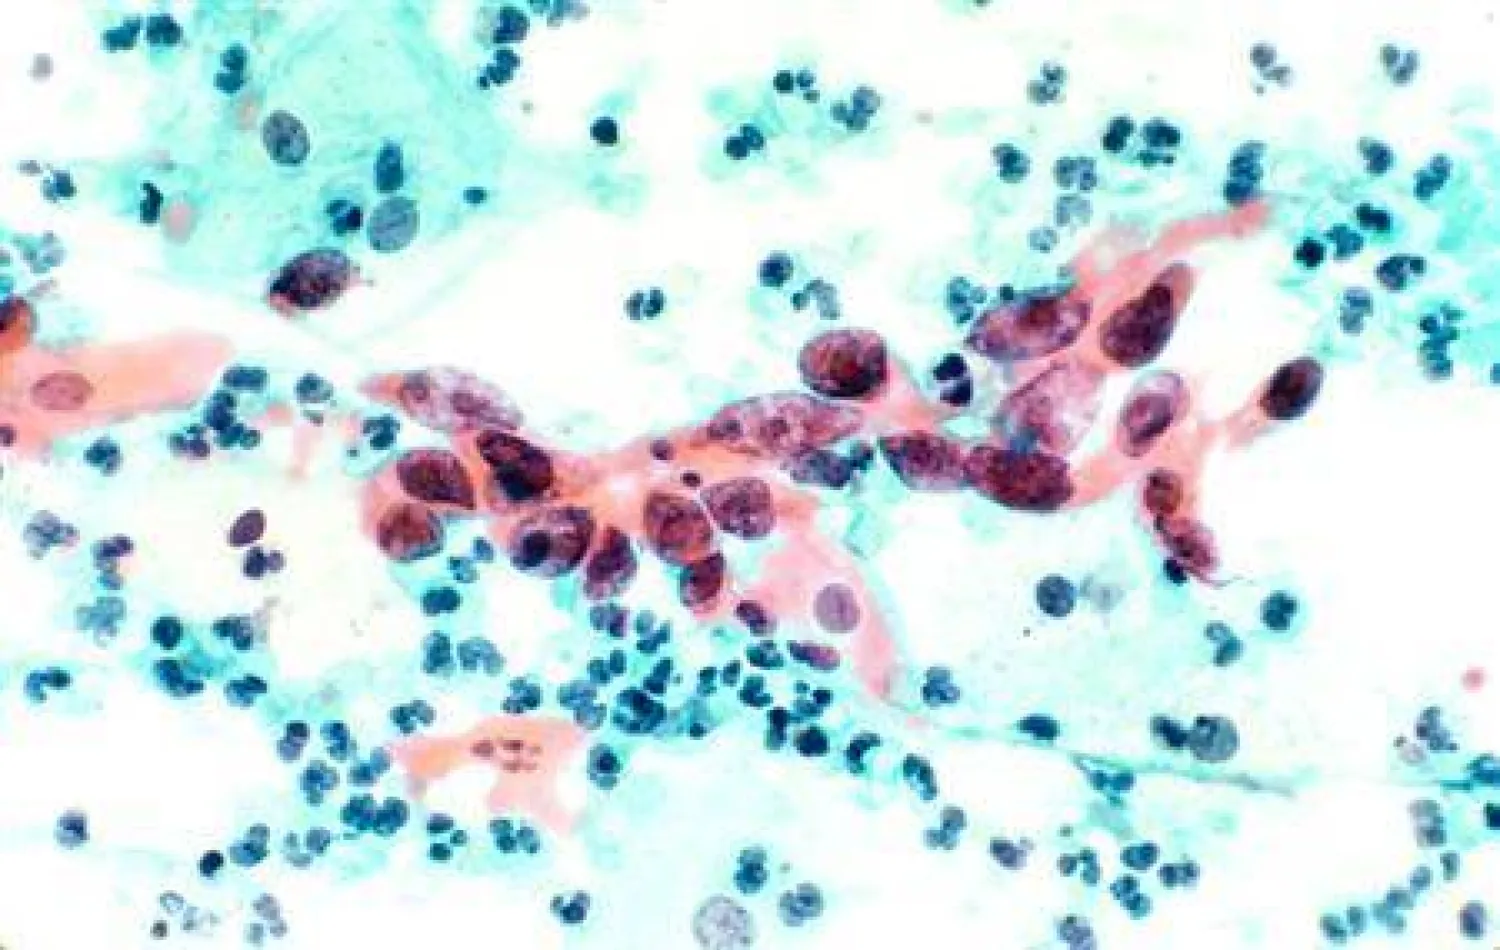

اكتشف علماء «طريقة فريدة» جديدة للاتصال يمكن أن تحول الخلايا لسرطانية؛ عندما تنقسم خلية واحدة إلى خليتين، يتم ترك قطعة صغيرة من المادة الخلوية، فقد أدرك العلماء للتو كيف يمكن لمحتوياتها تحويل الخلايا السليمة المجاورة إلى خلايا سرطانية سريعة الانقسام. إذ يُطلق على هذه القطعة اسم «بقايا منتصف الجسم»، ويبلغ حجمها جزءًا من المليون من المتر؛ وهي مليئة بالتعليمات الجينية لتقسيم الخلايا.

وأضافت سكوب «قبل أن نصل إلى ما تفعله الأجسام الوسطى، دعونا أولاً نفهم كيف تتشكل. فعندما تنقسم خليتان في الجسم بعملية تسمى الانقسام الفتيلي، يحدث قدر كبير من الخلط الداخلي. تتضاعف الكروموسومات وتصطف أسفل الخط الأوسط للخلية، ما يؤدي إلى ظهور أنابيب دقيقة مغزلية لسحب نسخة واحدة من كل كروموسوم في اتجاهات مختلفة لإنشاء خليتين ابنتين جديدتين. فيتجمع الجسم الأوسط عند الأطراف المتداخلة والممتدة للأنابيب الدقيقة المغزلية التي تربط نفسها بالكروموسومات. ومن هناك، يقوم الجسم الأوسط بتجنيد ووضع آلية الانفصال التي تقسم الجسر الأخير الذي يربط الخلايا المنقسمة إلى قسمين، فيتم إنجاز المهمة؛ ويُعتقد أن بقايا الجسم الأوسط تتحلل داخل الخلايا الوليدة. لكن الدراسات كشفت أن معظم هذه الطرود يتم إطلاقها فعليًا في الفضاء خارج الخلية وتبتلعها خلايا أخرى مجاورة. لكن ما وجده الباحثون بعد ذلك بدأ في الكشف عن الطبيعة الحقيقية لبقايا منتصف الجسم، كحزم إشارات الخلية، وليس صناديق القمامة. إذ تلتهم الخلايا السرطانية، التي تنقسم دون رادع، والخلايا الجذعية، وهي سلائف بلاستيكية تتطور إلى أنواع أخرى من الخلايا، بقايا منتصف الجسم أكثر من الخلايا العادية. وقد وجدت الدراسات أيضًا أن الخلايا التي تبتلع بقايا الجسم الأوسط تصبح أكثر غزوًا، ما يشير إلى دور بقايا الجسم الأوسط في إعادة برمجة الخلايا وانتشارها. لكن هذا مجال ناشئ، وقد بدأ فهم آليات إرسال الإشارات الخلوية لبقايا الجسم الأوسط للتو».

بدوره، كتب فريق الدراسة بورقته المنشورة «وجدت سكوب وزملاؤها أن بقايا الجسم الأوسط كانت محملة بأنواع معينة من الحمض النووي الريبي (RNA): تلك البروتينات التي تشفر البروتينات المشاركة في تكاثر الخلايا، وتعدد القدرات (قدرة الخلايا الجذعية على التطور إلى أي نوع من الخلايا)، وتولد الأورام (حيث تتحول الخلايا السليمة إلى خلايا سرطانية). والأكثر من ذلك، أن بقايا الجسم الأوسط تحتوي أيضًا على الآلية الخلوية اللازمة لتحويل هذا الحمض النووي الريبوزي (RNA) إلى بروتينات وظيفية. فعندما يتم إطلاق بقايا الجسم الأوسط، تنشغل تلك الآلية بترجمة الحمض النووي الريبوزي (RNA) إلى بروتينات، كما لو أن الكبسولة تستعد لمهمتها التالية في التواصل بين الخلايا».